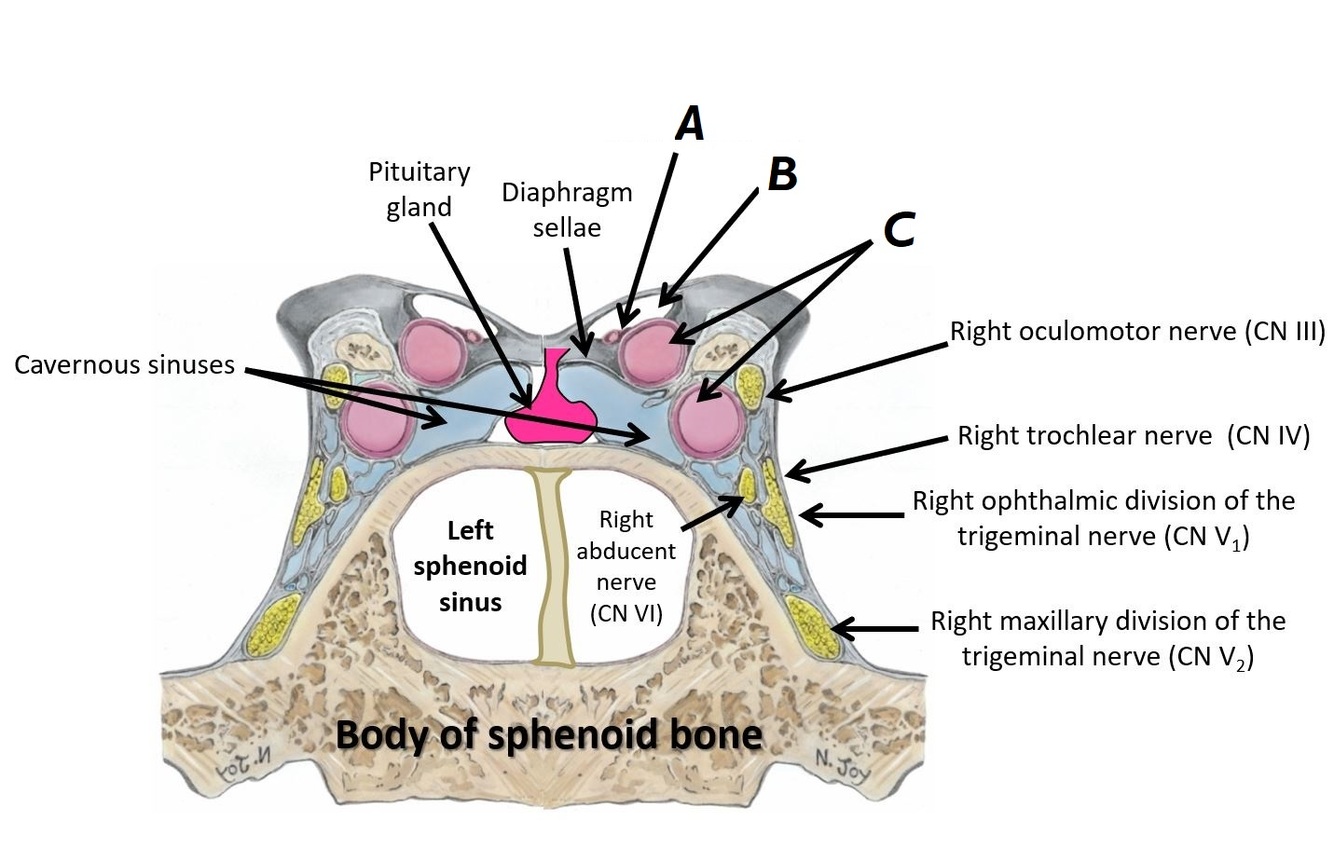

Name nerves A to D

A - Oculomotor nerve (CN III)

B - Trochlear nerve (CN IV)

C - Trigeminal nerve (CN V)

D - Abducens nerve (CN VI)